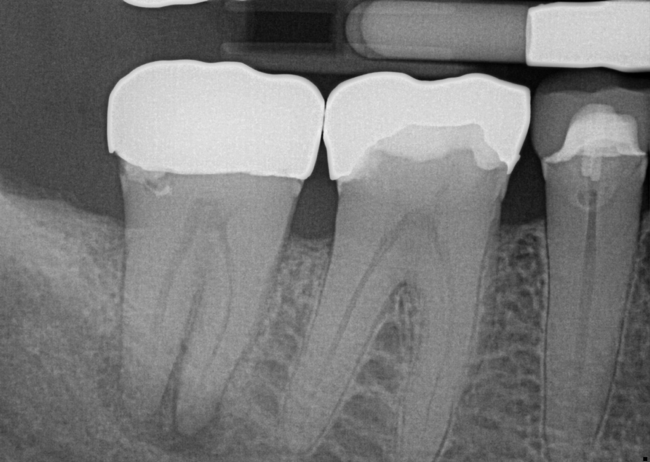

Fig 7. Primary endodontic and secondary periodontal lesion, mandibular second molar.

Figure 7

In Figure 7, the periapical radiograph identifies the presence of the combined endodontic-periodontal lesion developing due to a carious lesion beneath an existing vintage gold crown with ill-fitting margins. Intraoral examination revealed a fistula developing and moderate pain on percussion and mastication. After occlusal access and clear visualization of the canals, the canals were shaped using the rotary files, with precautions taken not to perforate or enlarge the apical foramen. Maintaining the endodontic therapy within the canals prevents the infection from being introduced into the surrounding periodontium. In this case, calcium hydroxide medicament was placed into the canals and evaluated 30 days postoperatively.8